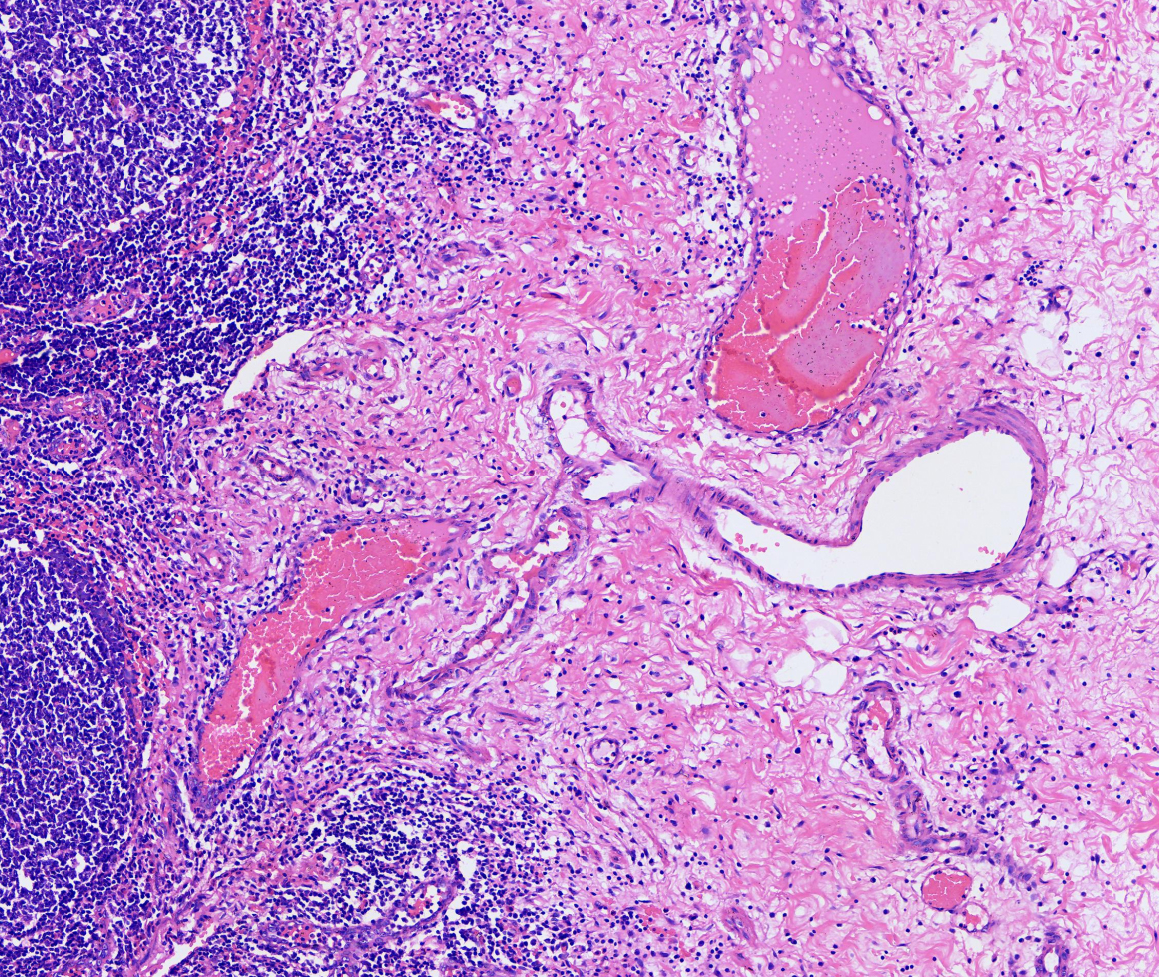

HE

院校/单位:广州市粤斌医学研究有限公司

样本种属:人

组织名称:阑尾

实验日期:2024-08-20